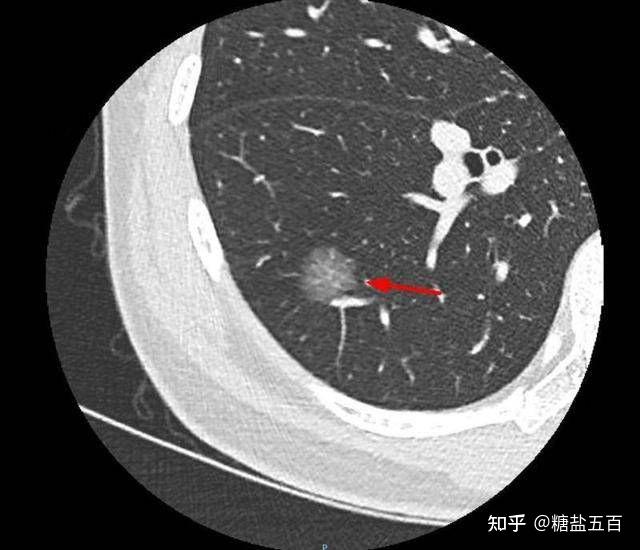

混合磨玻璃结节,伴有胸膜牵拉——肺腺癌